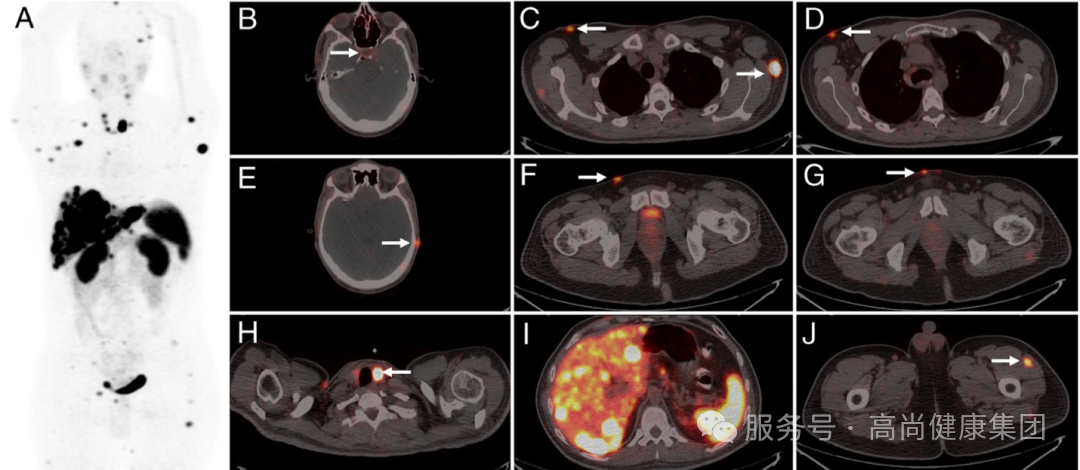

29 岁男性,9 年前诊断为肺类癌,因「多尿、烦渴、头痛及恶心」就诊。体检发现多发皮下结节,腹部 CT 提示肝脏多发占位,患者行 68 Ga-DOTA-TATE 以明确是否发生类癌转移。[3]

(A,MIP 图及 I,横轴位图),68 Ga-DOTA-TATE PET/CT 显示肝脏病灶摄取 DOTA-TATE 明显增加。

(B,轴位 PET/CT 图像),正常垂体因生理性摄取 68 Ga-DOTA-TATE 呈现高摄取,因患者全垂体功能减低,故垂体未见摄取增高。

(C-G,横轴位 PET/CT),68 Ga-DOTA-TATE 显示全身多处皮肤及皮下结节。

(H)显示甲状腺左侧叶局灶性高摄取。

(J)左侧股外侧肌肌间隙内转移灶。患者行肝穿刺活检,病检提示类癌转移。类癌全身均可发生,但以胃肠道和支气管肺组织最为常见。发生在肺部的类癌站全部肺原发肿瘤的 1%-2,尤其罕见。肺部类癌往往转移到纵膈、肝脏和骨;转移到皮肤的类癌比较罕见。[3]